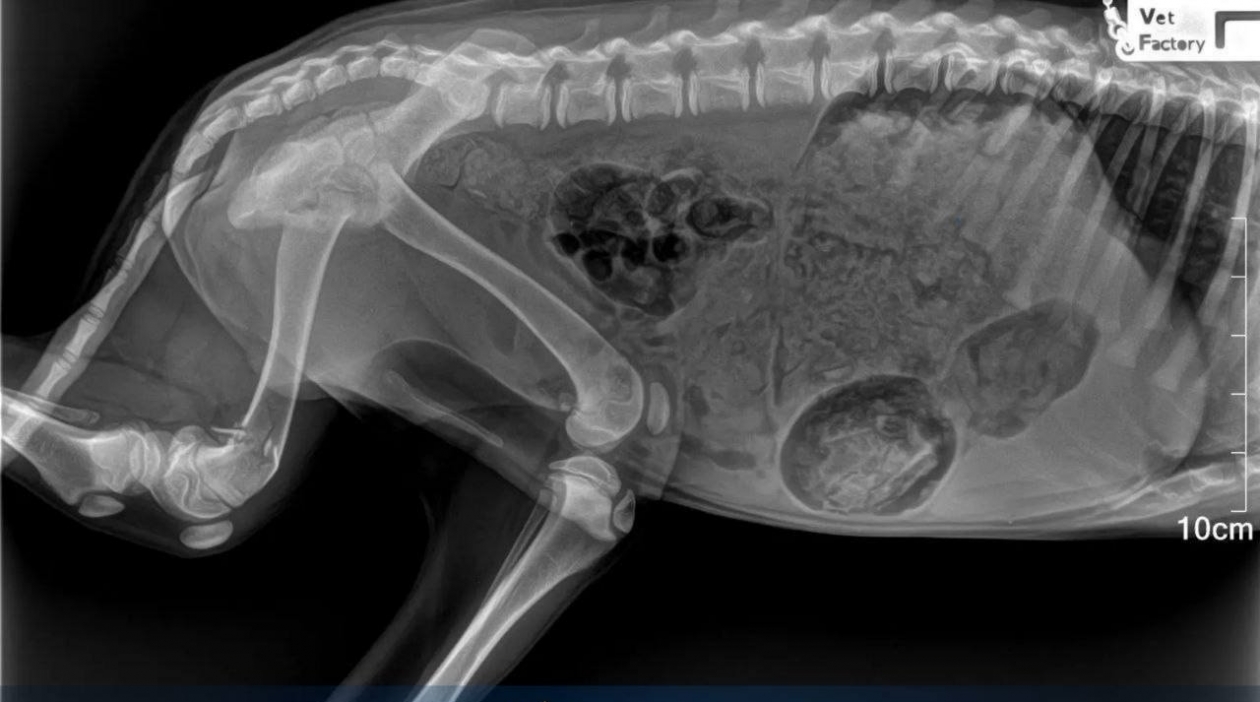

PrimaMedia, 27 января. Следствие устанавливает личность человека, выбросившего собаку из окна жилого дома в Лесозаводске. Четвероногая жертва чудом выжила, но получила множественные переломы, сообщила пресс-служба прокуратуры Приморья.